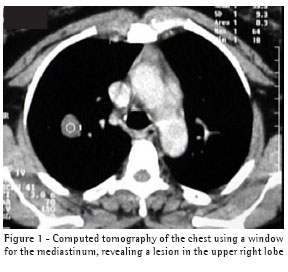

The results of the physical examination were normal, and the following complementary examinations were performed: chest X-ray; computed tomography of the chest; spirometry; intradermal reaction to purified protein derivative; Aspergillus serology test; fiberoptic bronchoscopy with bronchoalveolar lavage; and bronchial brush of the right segment. The chest X-ray revealed a nodule with well-defined borders in the upper third of the right hemithorax. The computed tomography of the chest (Figure 1) revealed a nodule with regular borders, measuring 2 cm, located in the apical segment of the upper right lobe. The nodule in reference presented contrast medium impregnation, with an increase of 26.7 Hounsfield units within three minutes after the injection of the venous contrast, and a central area of apparent cavitation. The analyses of the bronchoalveolar lavage and bronchial brush revealed negativity for neoplasm. The culture for acid-fast bacilli was also negative, as were the cultures for tuberculosis, fungi and bacteria.

The chest X-ray finding is frequently a singular well-delineated nodule.(2) In this case, computed tomography of the chest revealed a nodule with well-defined borders and presenting an increase of 26.7 Hounsfield units after impregnation by contrast (Figure 1). In one study, it was reported that 98% of benign nodules presented highlighting by contrast of 15

Hounsfield units or less.(7) In the present case, the use of contrast in the computed tomography did not follow the recommendations of that study.